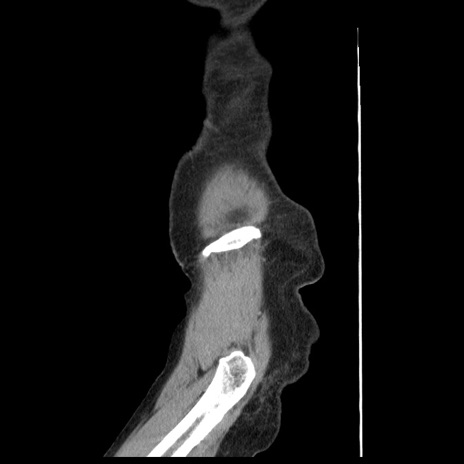

横断像